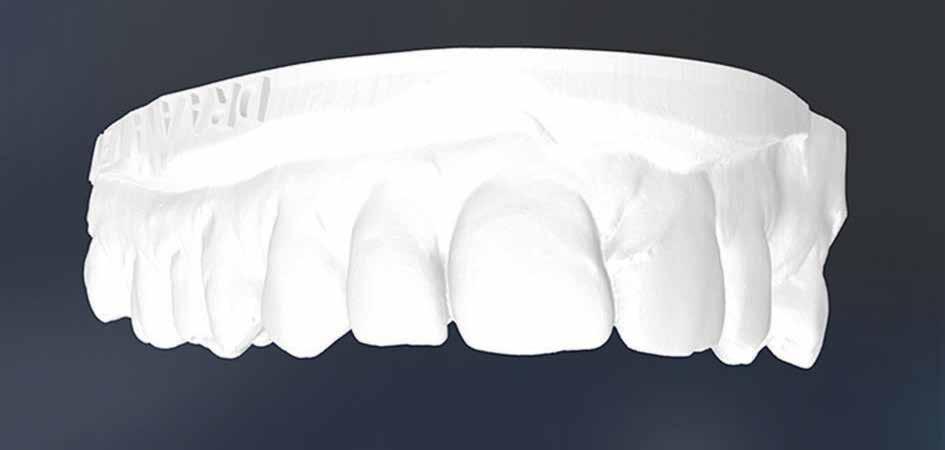

A felső állcsontról intraorális szkent (TRIOS) készítettünk, és az ezáltal kapott STL fájlt (2. d. ábra) a CBCT-felvétel során nyert DICOM fájlokkal a Zirkonzahn.Implant-Planner (Zirkonzahn) szoftverben egyesítettük. A sebészi sablont ebben a programban megterveztük, majd a Meshmixer (Autodesk) szoftver se-

a-m. ábrák: Preoperatív röntgenfelvétel (a) és preoperatív CBCT-felvétel a jobb felső 5-ös (1.5) fogról, sagittalis (b) és axialis (c) nézetek. Az intraorális szkennelés során kapott STL-fájl (d). A 1.5-ös fog navigált endodonciai mikrosebészeti beavatkozásához tervezett sablon (e). A 1.5-ös fog navigált endodonciai mikrosebészeti beavatkozásához nyomtatott sablon (f). Teljes vastagságú mucoperiostealis lebenyt emeltünk (g). A sablont a helyére illesztettük, és a csontablak határait jelöltük (h). A fog gyökerén kívül eső, betört eszköz a 1.5-ös fog periapicalis régiójában (i). Az eltávolított betört eszköz (j). A rezekció, retrográd preparáció és a TotalFill BC RRM Fast Set Putty anyaggal elkészített retrográd gyökértömés utáni röntgenfelvétel (k). A lebenyt varratokkal rögzítettük (l). A kétéves kontroll során készített röntgenfelvétel (m).